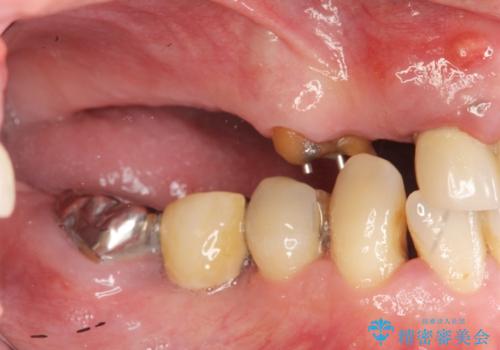

多発した虫歯による咬合崩壊 インプラントを用いた全顎治療

歯の破折・再発した大きな虫歯・根尖病変・歯の欠損、これらの問題を根管治療・歯周外科・インプラント治療・セラミック補綴を行うことで一つづつ解決し安定した咬合状となるよう治療を進めます。

インプラント治療の注意事項(リスク・副作用など)

- 外科手術のため、術後に痛みや腫れ、違和感を伴います

- メンテナンスを怠ったり喫煙により、お口の中に大きな悪影響を及ぼすインプラント周囲炎等にかかる可能性があります